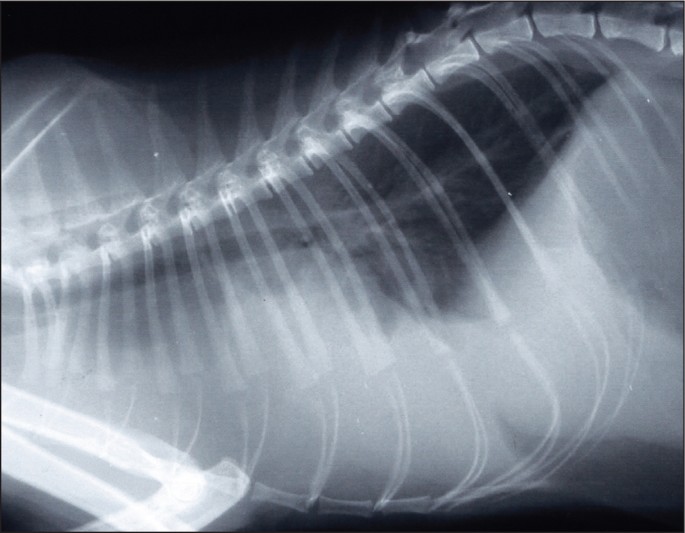

고양이 심비대 및 심잡음

비대성심근병증